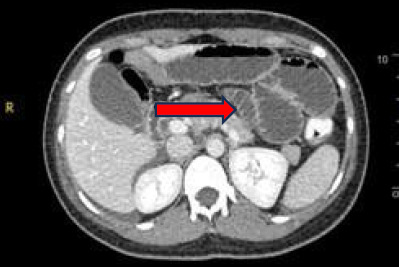

尿淀粉酶水平通常用于诊断急性胰腺炎。不过,也有报告称,没有胰腺炎的人尿淀粉酶水平也会轻微升高。在此,我们报告了一位年轻女士的病例,她因急性腹痛 3 天而就诊。入院时她的尿淀粉酶水平为 1717 U/L,她的病情最初被当作急性胰腺炎治疗。不幸的是,24 小时后患者出现腹部不适,因此紧急进行了计算机断层扫描(CT)检查。CT 显示小肠扩张。她接受了急诊开腹手术,术中发现小肠坏疽,小囊处无皂化迹象。由于高淀粉血症的非特异性,如果临床症状不能提示胰腺炎,或者尽管采取了保守治疗但病情仍恶化,则应考虑急性胰腺炎以外的其他诊断。

Urine amylase levels are usually used to diagnose acute pancreatitis. However, there are reported cases where urine amylase levels are slightly increased in individuals without pancreatitis. Herein, we report the case of a young lady who presented with acute abdominal pain for 3 days. Her urine amylase level was 1717 U/L upon admission, and her condition was initially treated as acute pancreatitis. Unfortunately, the patient demonstrated abdominal guarding after 24 h; thus, urgent computed tomography (CT) was performed. CT revealed the presence of a dilated small bowel. She underwent emergency laparotomy, wherein a gangrenous small bowel with no evidence of saponification at the lesser sac was noted. Due to the non-specific nature of hyperamylasaemia, an alternative diagnosis other than acute pancreatitis should be considered if the clinical symptoms are not suggestive of pancreatitis or the condition worsens despite conservative management.